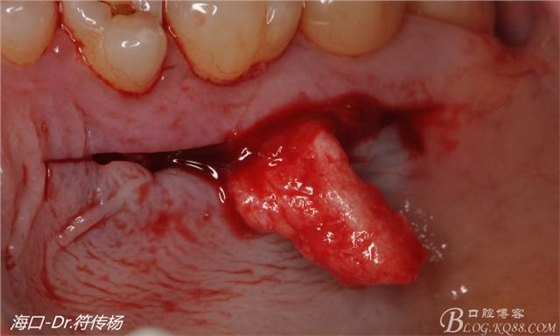

接著從腭部上皮下取出結(jié)締組織

確定取出結(jié)締組織長(zhǎng)度是否適當(dāng)

腭部使用水平懸吊縫合更利于壓迫止血